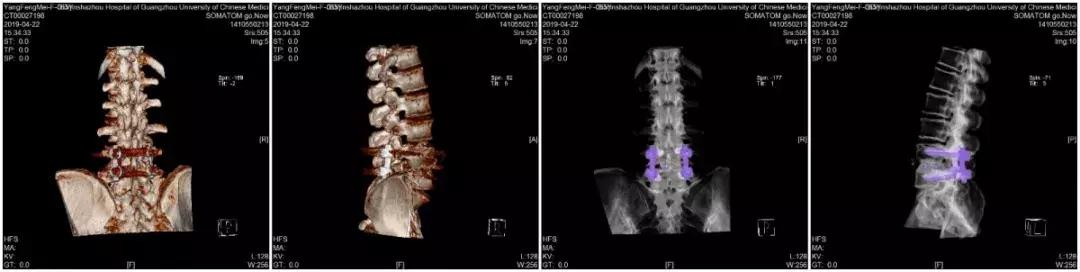

影像学检查

3、手术治疗:对于椎管狭窄的治疗是针对脊柱骨骼结构的治疗。

2)椎板切除、神经根减压是基本的手术方式。